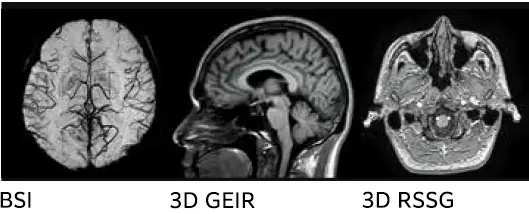

Görüntü kalitesini artırmaya yönelik donanım teknolojilerimiz

Güçlü RF çıkışı stabil RF iletimine katkıda bulunur.

ECHELON Smart Plus 18 kW RF güç çıkışı ile donatılmıştır. Bu, kesintisiz olarak yeniden netleme pulsları uygulayan FSE sekansında bile görüntü kalitesinde bozulma olmadan net görüntüler sağlamak için yeterlidir.